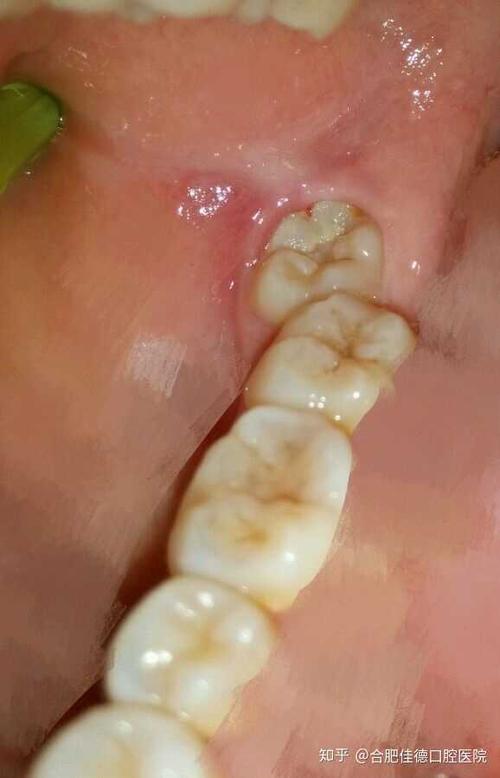

问:请问这样的智齿要拔吗?不痛,要用力舔才有一点感觉.

我的智齿长得很正常,和普通牙齿一样高,一样垂直,只是

智齿正常的图片

正常的智齿图片

智齿发炎

智齿图片

智齿是什么样子的

不需要拔的智齿图片